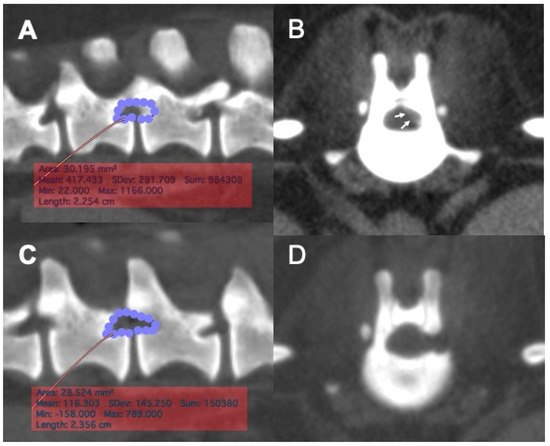

2.6. Imaging Analyses

Pre- and post-operative CT images were exported in the DICOM (Digital Imaging and Communication in Medicine) format to a commercial imaging software for imaging analyses. The planned craniocaudal and dorsoventral borders of laminectomy were defined as described and the area of laminectomy was obtained by manually tracing the defined borders, using the preoperative CT images (Figure 2A,B). On post-operative CT images, the length and area of laminectomy were measured. The area of laminectomy was measured by manually tracing the border of the bone defect (Figure 2C,D).

3.4. Morphometric Analyses

Post-operative CT images were obtained immediately after surgery in eight cases. The laminectomy dimensions were measured on post-operative CT imaging and the extent of laminectomy was compared to the planned region for eight laminectomies in seven cases that underwent full endoscopic procedure (Figure 2A–D). The mean ± SD ratios of the actual length and area of laminectomy in relation to the planned length and area of laminectomy were 106.6 ± 16.1% and 109.1 ± 23.8%, respectively. There was an equal distribution of the number of cases that had received either smaller or bigger laminectomy than the planned laminectomy size. Data of individual cases are presented in Table 3.

Figure 2. Pre-operative planning and post-operative measurement of laminectomy area with reconstructed CT images. (A), The area of the planned laminectomy window was determined based on the location of the extruded disc material in the vertebral canal, using a reconstructed sagittal CT image. The area of planned laminectomy in this case was 30.2 mm2. (B), A transverse CT image of the intervertebral disc space was used to aid determining the location of the extruded disc material (arrows) in the vertebral canal. (C), A post-operative reconstructed sagittal image of the surgical site. The region of laminectomy was traced, and the area of actual laminectomy size was obtained. The actual area of laminectomy in this case was 28.8 mm2. (D), A post-operative transverse CT image of the surgical site showing the location of mini-hemilaminectomy.